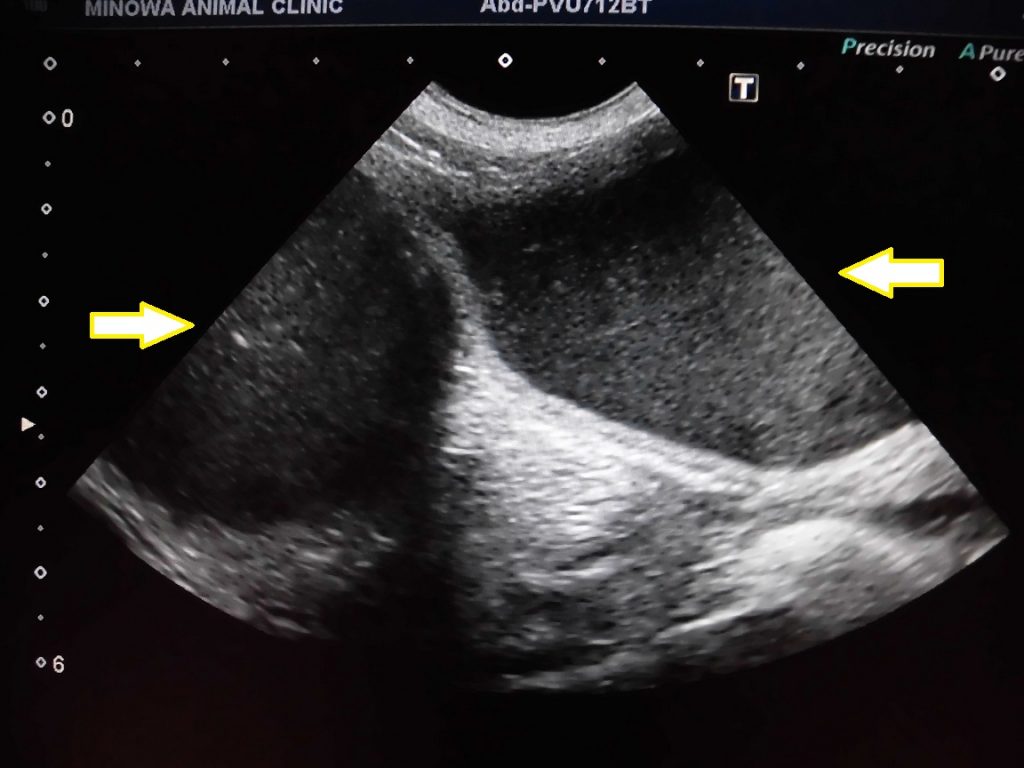

子宮蓄膿症は超音波検査を実施することで、拡張した子宮を確認することが可能です。

今回のわんちゃんも超音波検査で拡張した子宮と、その内部に蓄積した液体を確認することができました。